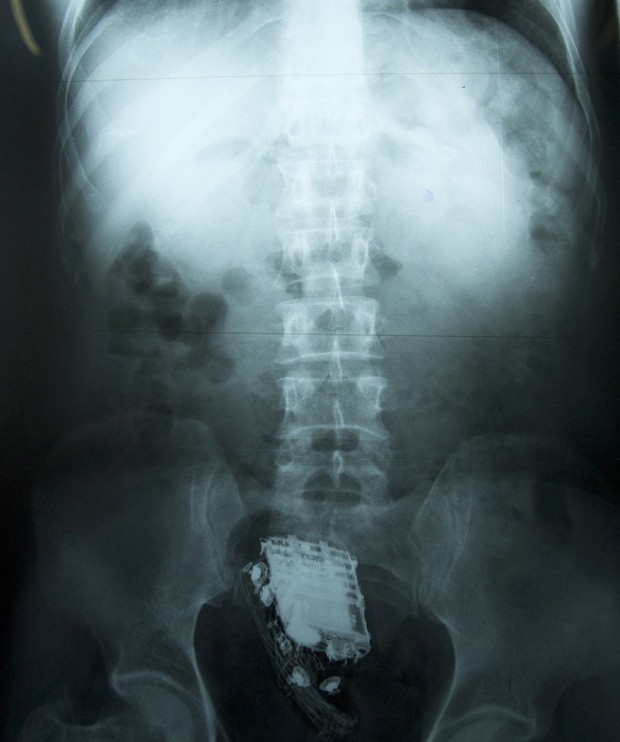

O condenado de 58 anos de idade precisou ser internado no hospital nacional em Colombo, onde os médicos mais tarde retiraram o aparelho de seu reto.

"O homem tinha escondido o telefone dentro dele mesmo", disse o funcionário, que pediu para não ser identificado.